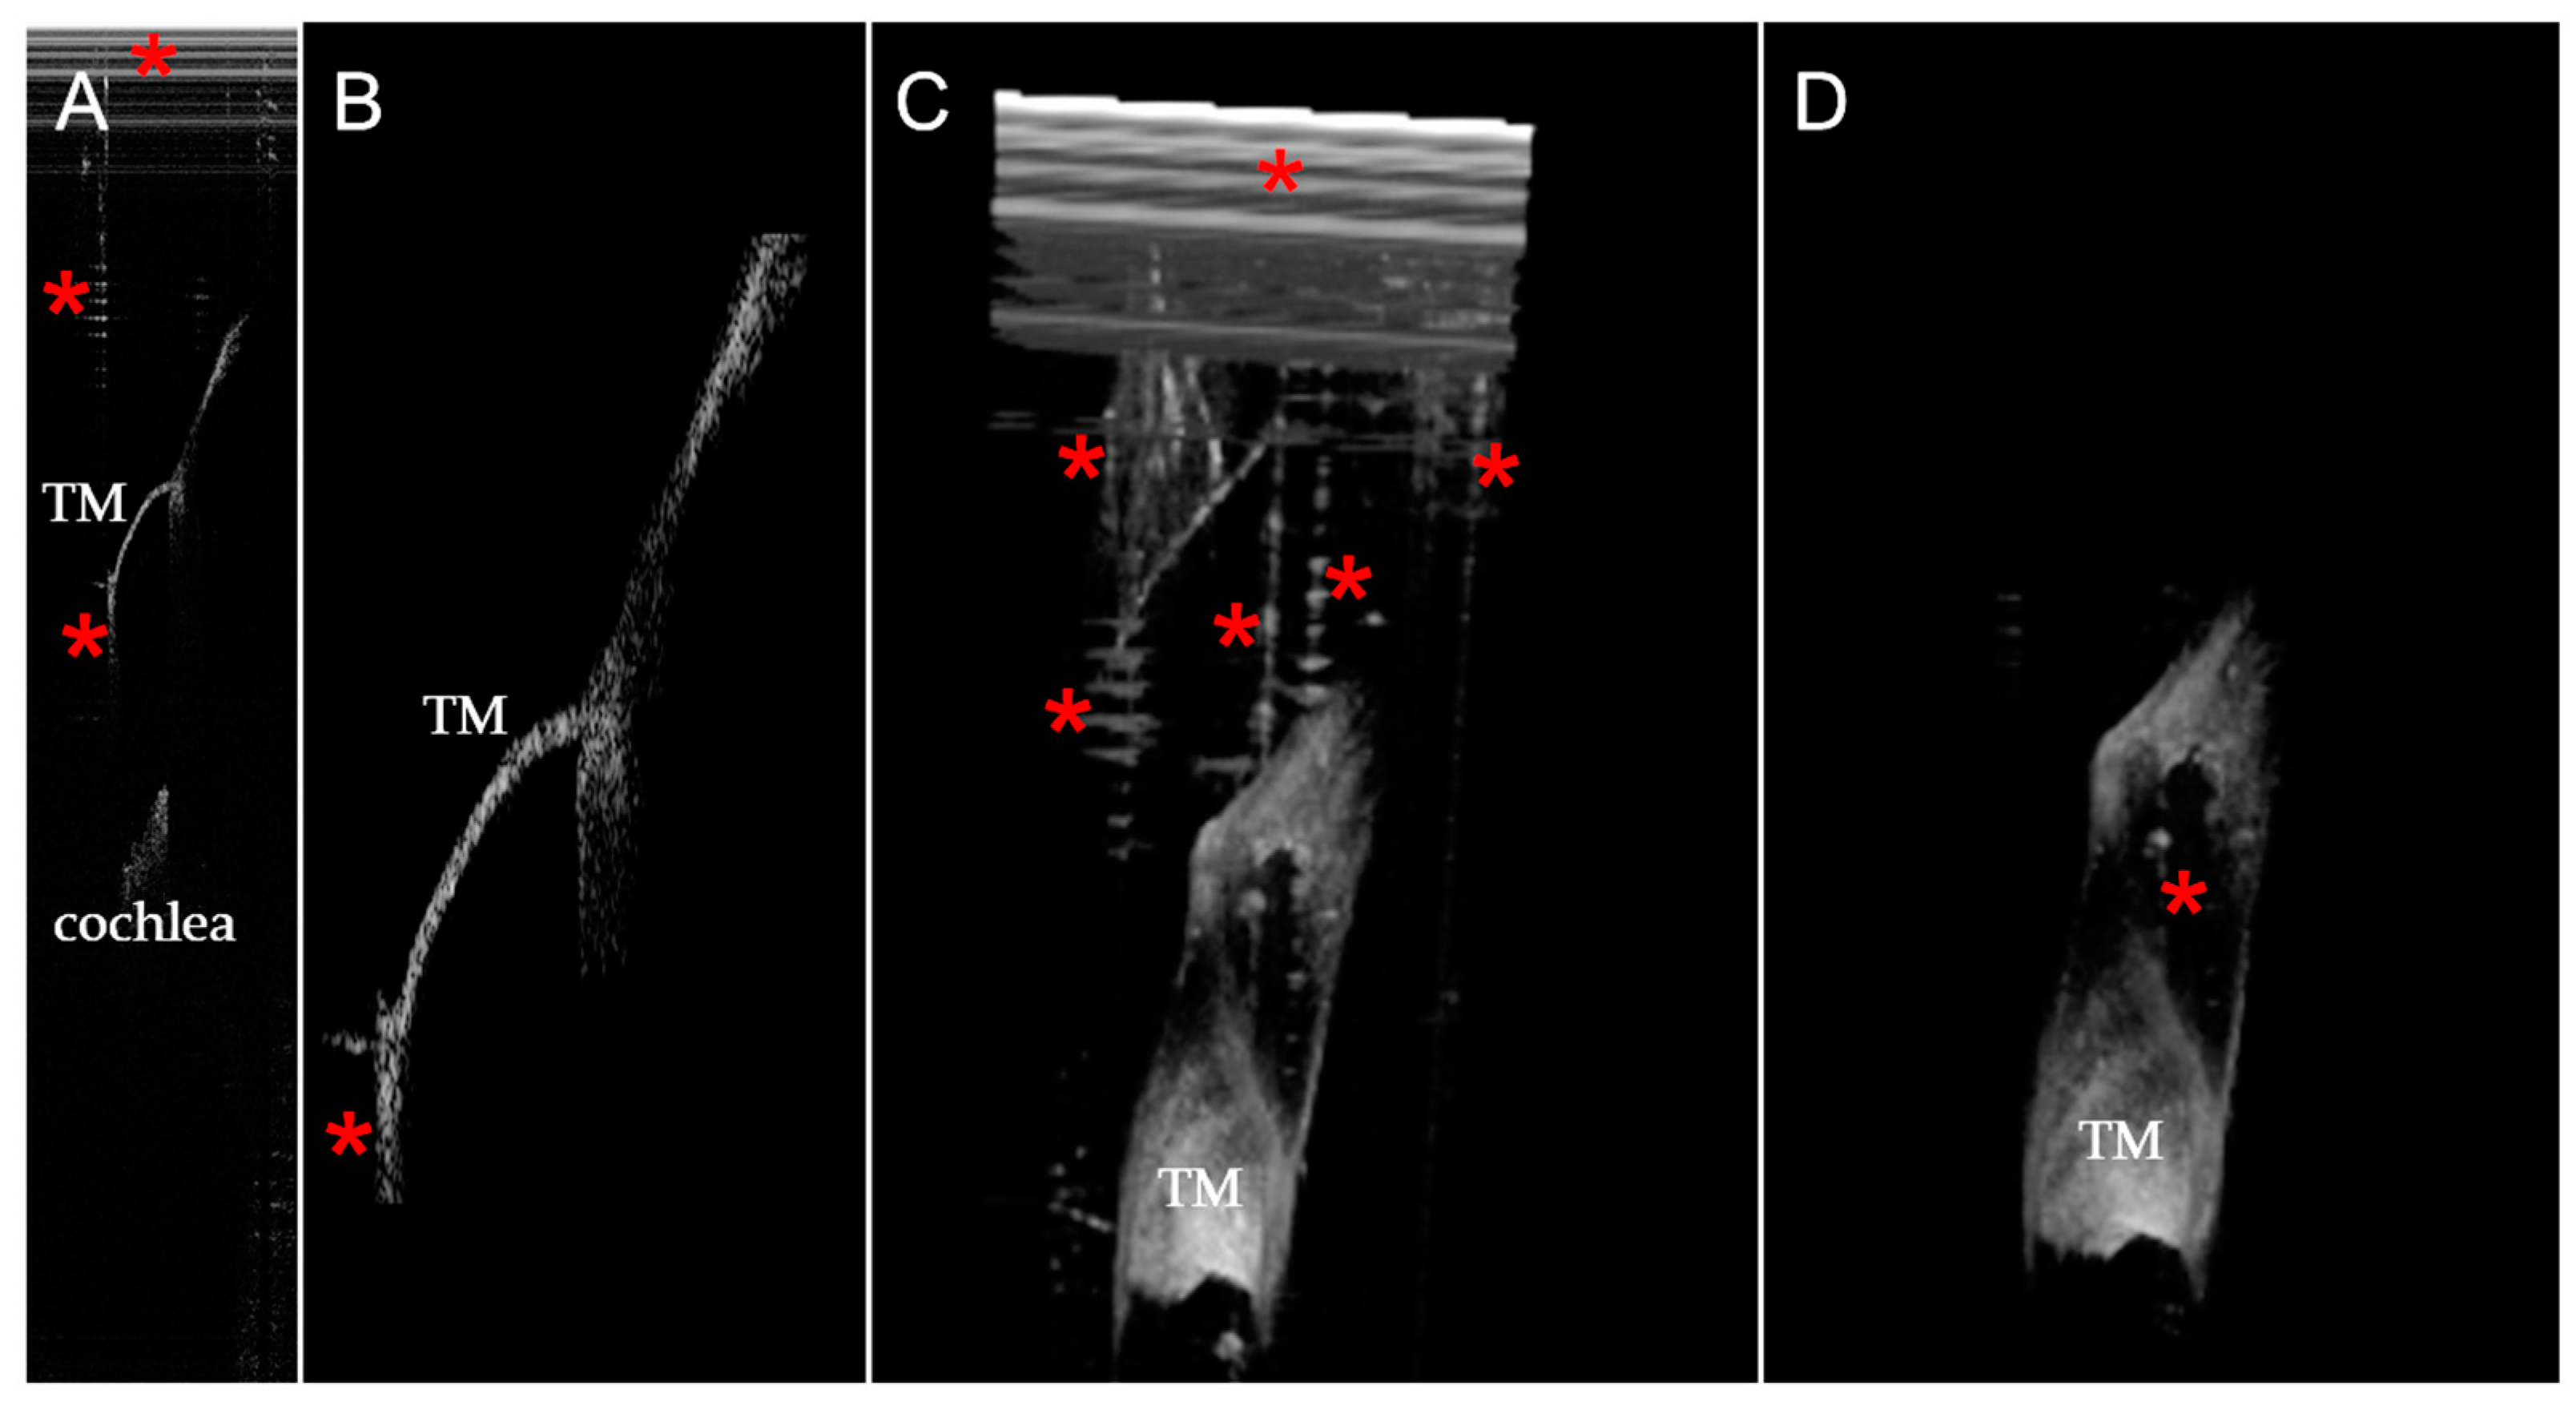

2.3. Large Object Detection Algorithm

2.4. Small Object Detection Algorithm

2.5. Image Recognition Algorithms

2.6. 3D Reconstruction Algorithm